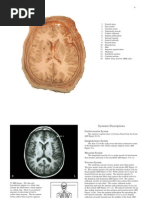

Axial multidetector CT

image

1. Caudate nucleus

2. Anterior limb internal

capsule

3. Lenticular nucleus

4. Inferior sagittal sinus

5. Superior sagittal sinus

6. Interhemispheric fissure

/ Falx cerebri

7. Thalamus

8. Lateral ventricle

9. Corpus callosum

Axial

multidetector

CT image

1. Superior

frontal gyrus

2. Lateral

ventricle

3. Caudate

nucleus

multidetector CT

1. Superior frontal

gyrus

2. Interhemispheric

fissure / Falx

cerebri.

Coronal

reconstructed

1. Frontal Gyri

2. Lateral rectus

muscle

3. Nasal turbinate

4. Maxillary sinus.

2. Zygomatic arch

3. Mandible

4. Nasal turbinate

5. Alveolar arch

6. Right maxillary

sinus

1. Interhemispheric

cerebri

2. Frontal Gyri

3. Corpus callosum

4. Lateral ventricle

5. Temporal gyri

6. Mandible

7. Sphenoid sinus.

reconstructed image

2. Superior frontal

3. Caudate nucleus

4. Third ventricule

5. Basilar artery

6. Lenticular nucleus

7. Internal capsule

2. Superior sagittal

3. Lateral ventricle

5. Temporo-

occipital Gyri

Sagittal

1. Oropharynx

2. Nasal turbinate

3. Frontal Gyri

4. Corpus callosum

5. Lateral ventricle

6. Cerebral trunk

7. Occipital gyri

8. Cerebellar

hemisphere

Sagittal reconstructed

1. Bony palate

2. Nasal fossa

3. Sphenoid sinus

4. Turcic sellae

6. Corpus callosum

7. Internal cerebral vein

8. Inferior sagittal sinus

9. Straight sinus

10.Confluens sinuum

11.Fourth ventricle

12.Cerebellar hemisphere

13.Pons